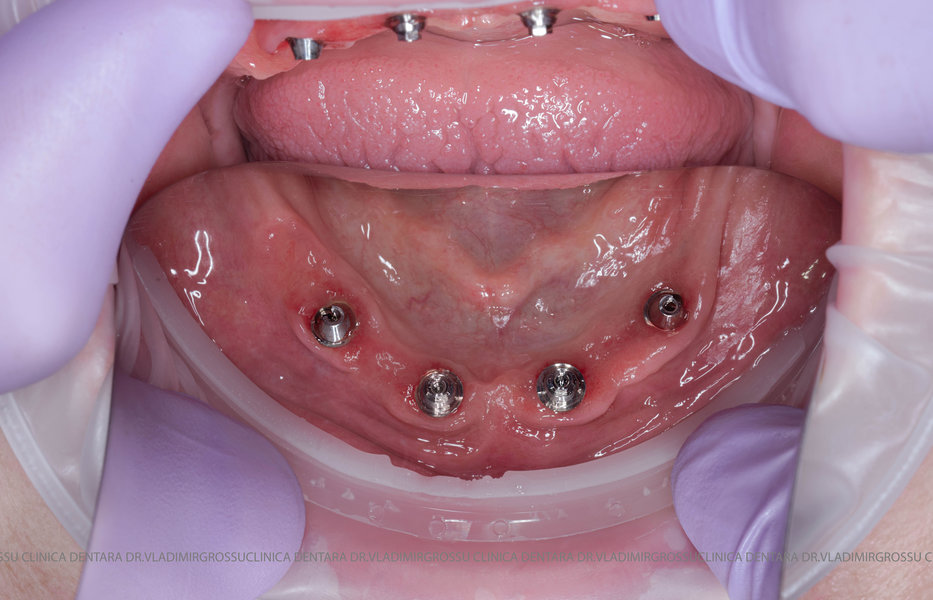

- 4 implanturi;

- 2 multiunit-uri drepte și 2 multiunit-uri angulate, conform necesităților protetice;

- 4 abutment-uri provizorii pe multiunit-uri;

- Proteză provizorie din masă plastică frezată sau proteză mobilizabilă pregătită și ajustată la componentele protetice.